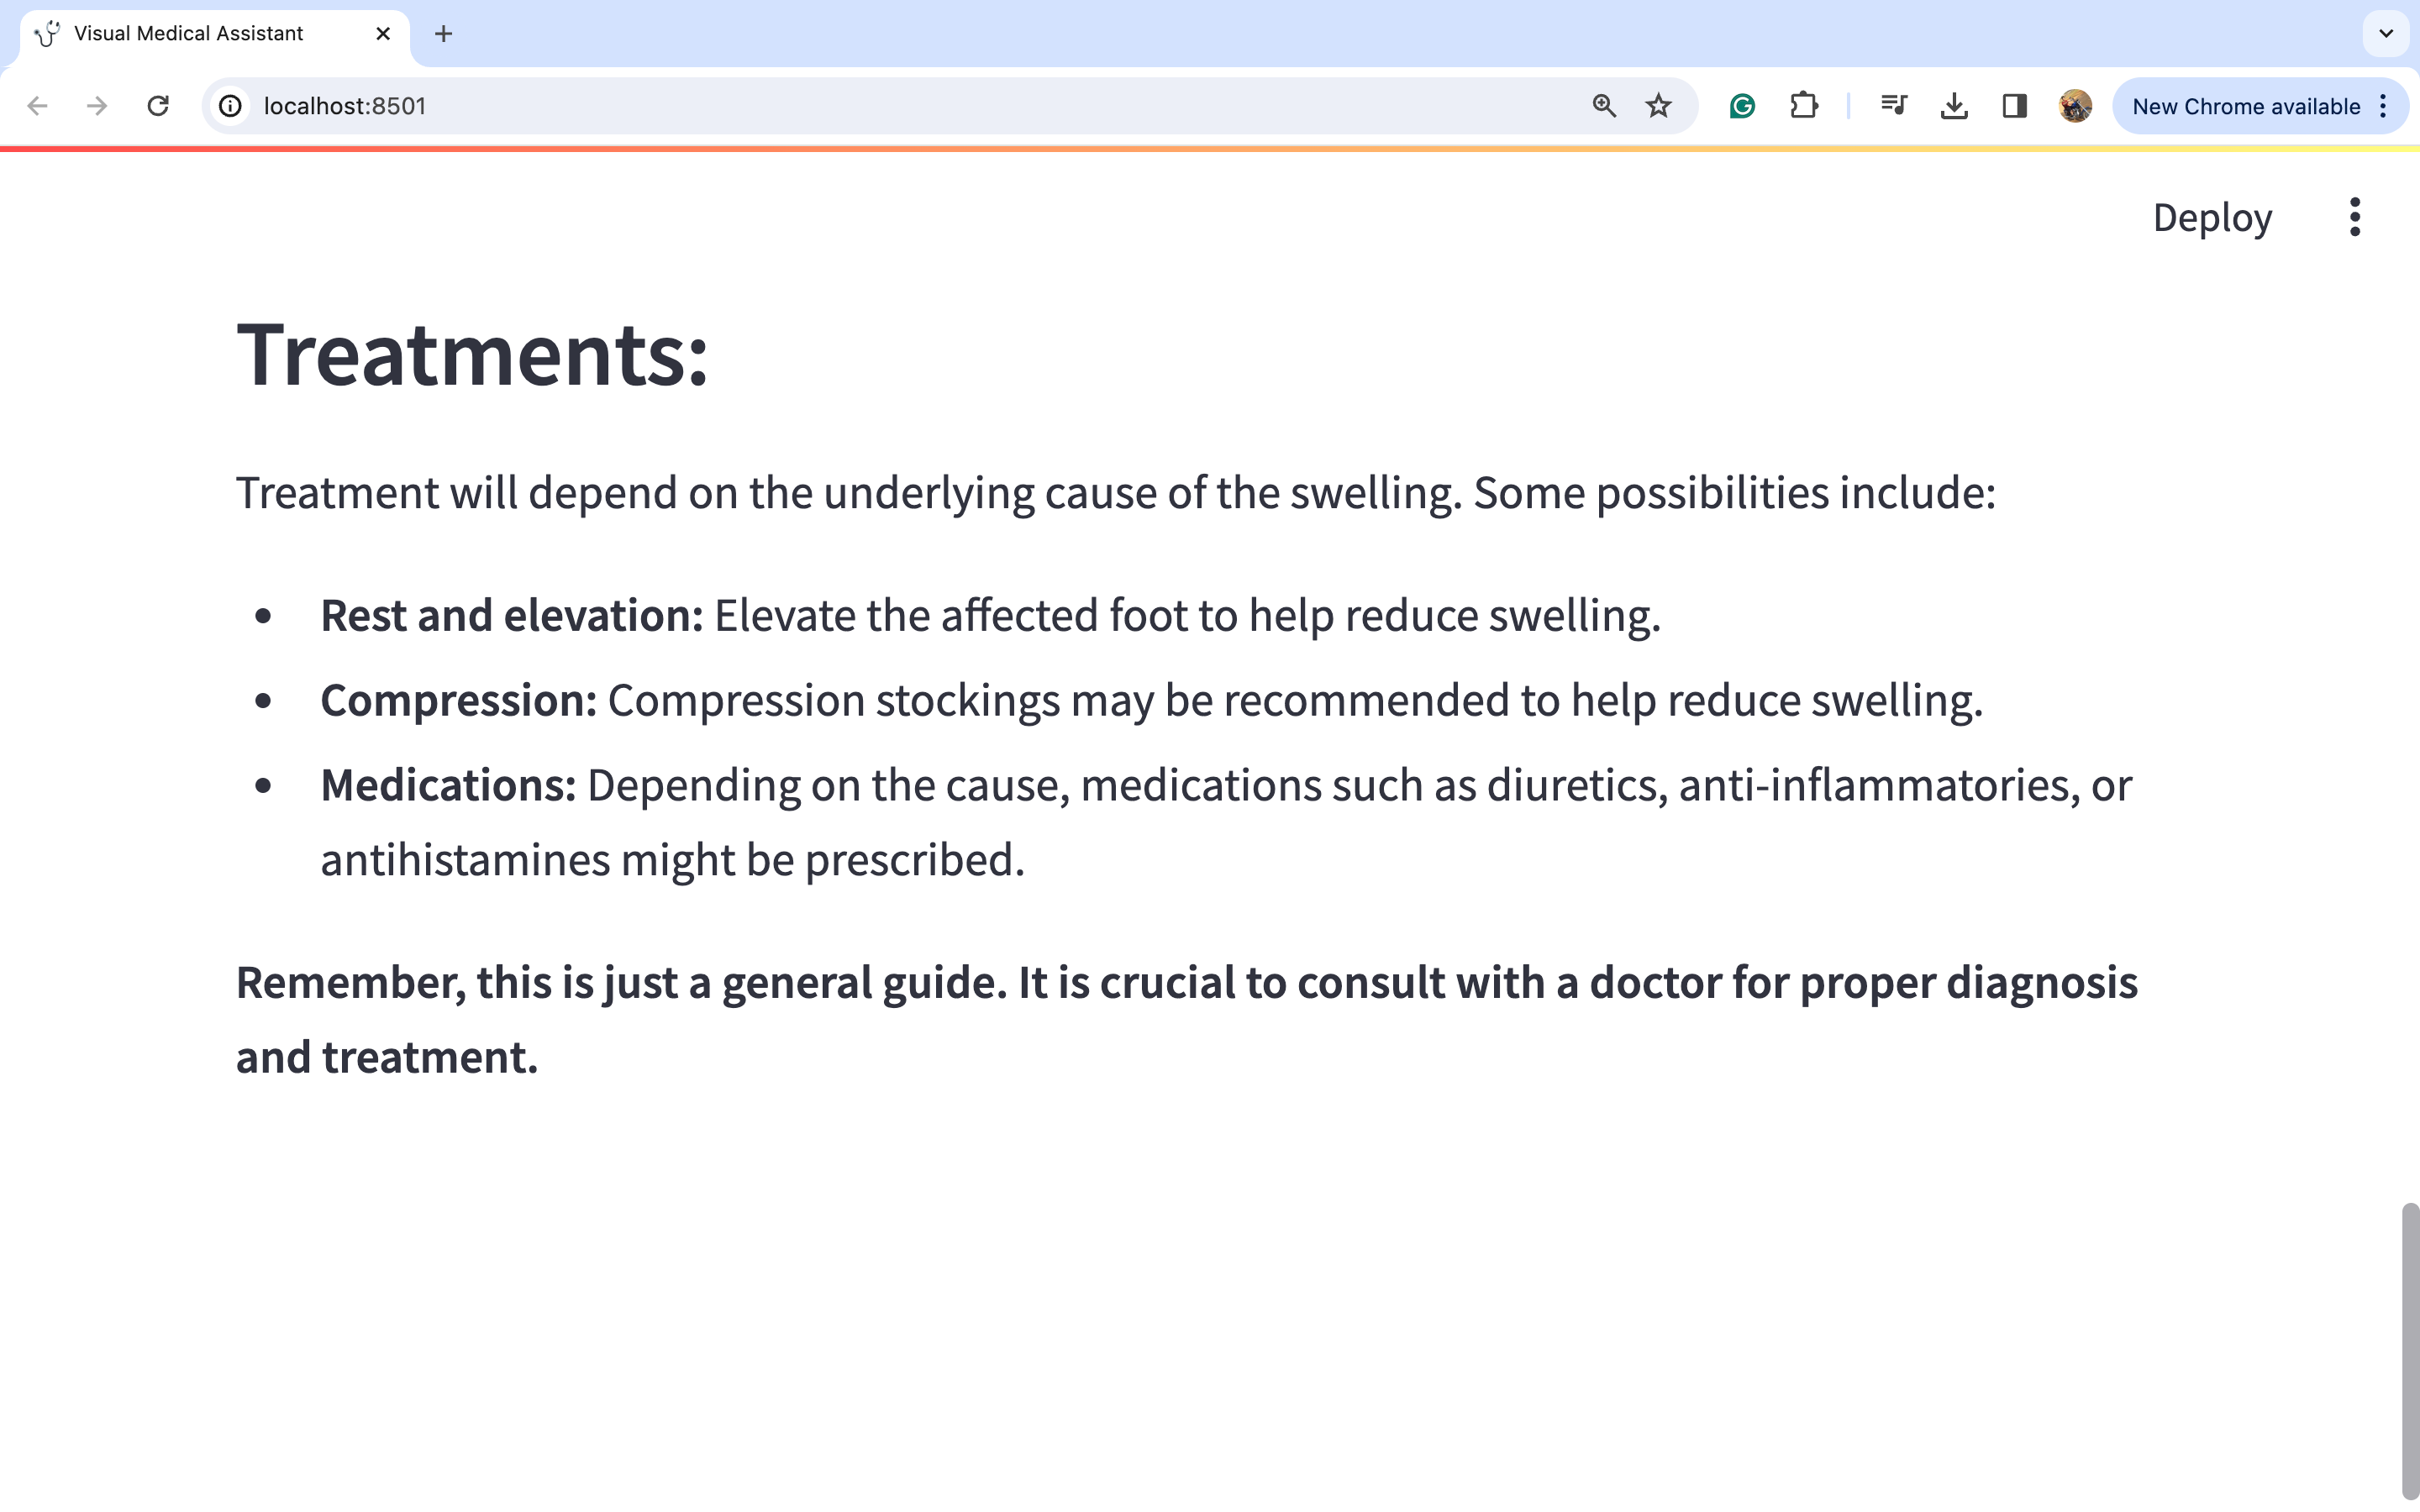

图片3:

因此,我们可以通过观察图片来进行深入的详细分析,从而得出可能的医疗诊断。我们可以看到模型如何捕捉到左脚肿胀的问题。模型建议咨询医生,因为仅仅通过观察这种肿胀很难得出很多结论。然而,我们可以看到一些治疗选择,如使用压缩包和抬高左脚以减轻肿胀,在这种情况下似乎是合理的选择。